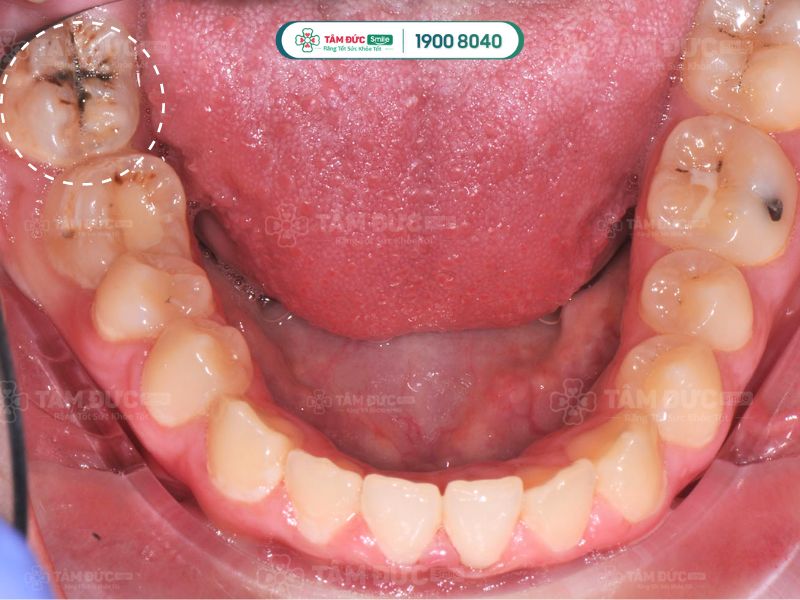

1.1. Kẽ răng bị đen do sâu răng

Sâu răng là nguyên nhân chủ yếu làm cho kẽ răng bị đen. Đây là bệnh lý răng miệng phổ biến, là hiện tượng mô cứng trên răng bị tổn thương trước sự tấn công của vi khuẩn. Các lỗ nhỏ li ti hình thành trên bề mặt răng, dần phát triển thành lỗ sâu răng to có màu đen, có thể nhìn thấy bằng mắt thường.

Sâu răng thường hình thành ở kẽ răng. Do đó, nếu Quý khách nhận thấy kẽ răng của mình bị đen thì có thể nghĩ ngay đến là do sâu răng gây ra.

kẽ răng bị đen do sâu răng

Kẽ răng bị đen do sâu răng gây ra